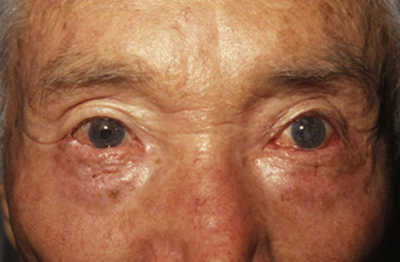

Dejamos un vendaje compresivo por 48 horas, antibióticos y antiinflamatorios por 7 días, controles post-operatorios cada tercer día. (Figura 16) El injerto fue cambiando de color, a medida que su integración se fue llevando a cabo, una vez integrado , dejamos abundante ungüento en el nuevo borde libre palpebral, en donde inicialmente se hacia visible el cartílago auricular , con el tiempo epitelizó completamente y pudimos retirar el lente de contacto blando. La conjuntiva tarsal se reduplicó sola, y el paciente fue dado de alta a los 2 meses de su cirugía reconstructiva. (Figura 17) Un control a los 6 meses muestra un resultado anatómico y fisiológico satisfactorio en párpado inferior Izquierdo. (Figura 18)

Figura 18 Post-operatorio 6 meses